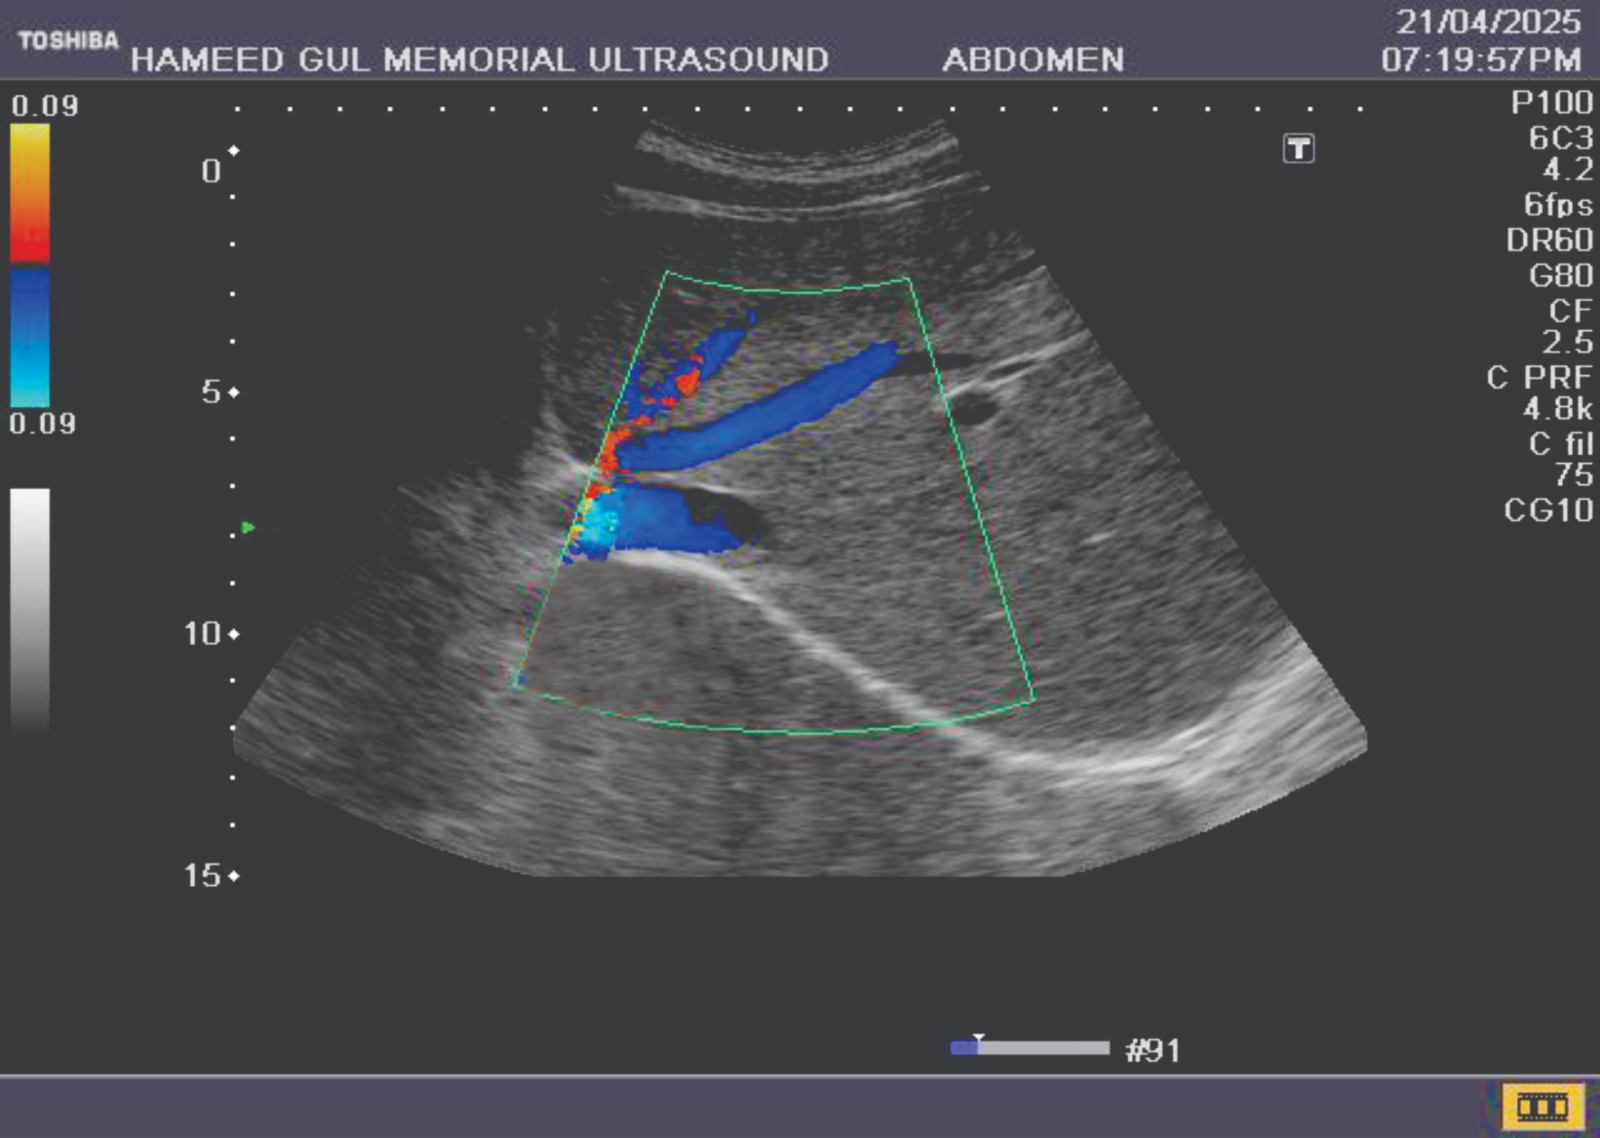

Detailed imaging of abdominal organs for diagnostic evaluation and assessment.

Liver and Gallbladder

Pancreas and Spleen

Kidney and Bladder

prostate, retroperitoneal

sub-phrenic, sub-hepatic

pleural spaces.

Vascular health: Carotid arteries, jugular veins, peripheral veins and arteries, abdominal aorta, and inferior vena cava.

Portage system: Portal hypertension, renal vessels in hypertension and renal failure.